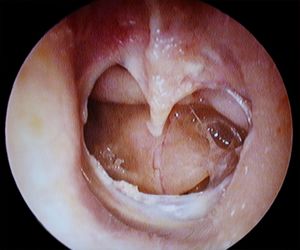

Middle Ear

- Results from inability to equalize middle ear pressure

- Pain, fullness, vertigo, conductive hearing loss, TM rupture